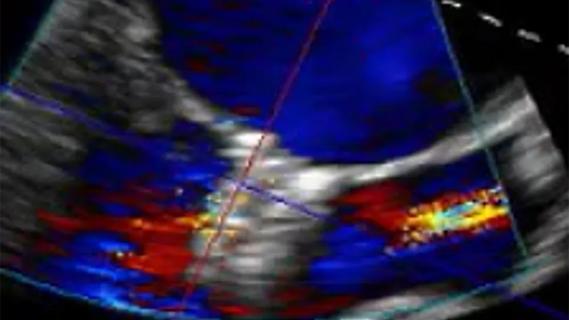

Additionally, the two pacemakers must be positioned correctly for direct communication — “eye to eye,” as he puts it — before they are released from the catheter. This is what allows the two devices to work together to achieve synchronous contraction between the upper and lower chambers of the heart, an essential feature for a dual-chamber pacemaker system.

Image at top courtesy of Abbott. The Aveir DR dual-chamber leadless pacemaker is an investigational device limited by federal (U.S.) law and medical device regulation for investigational use only.